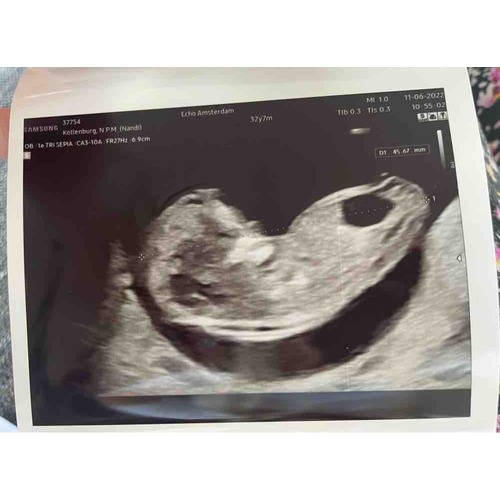

We zijn vanmiddag bij de gynaecoloog geweest. Als het een meisje is heeft ze geen kans. Als het een jongetje is kan het zijn dat de klepjes nog niet goed werken. Over 2 weken gaan we kijken hoe het eruit ziet. Als het er nog hetzelfde uitziet heeft de baby geen kans.

Een baby leeft in vruchtwater met urine. Als de blaas niet wordt geleegd dan wordt deze vanbinnen alsmaar groter en gaat alles kapot.

De baby is vol in beweging. Alles zit erop en eraan en op de juiste plaats. Maar als de baby niet kan plassen heeft het geen overlevingskans. We houden nog een sprankje hoop dat het gewoon een stout jongetje is. Als de blaas niet schijnt te werken is er waarschijnlijk idd meer aan de hand.